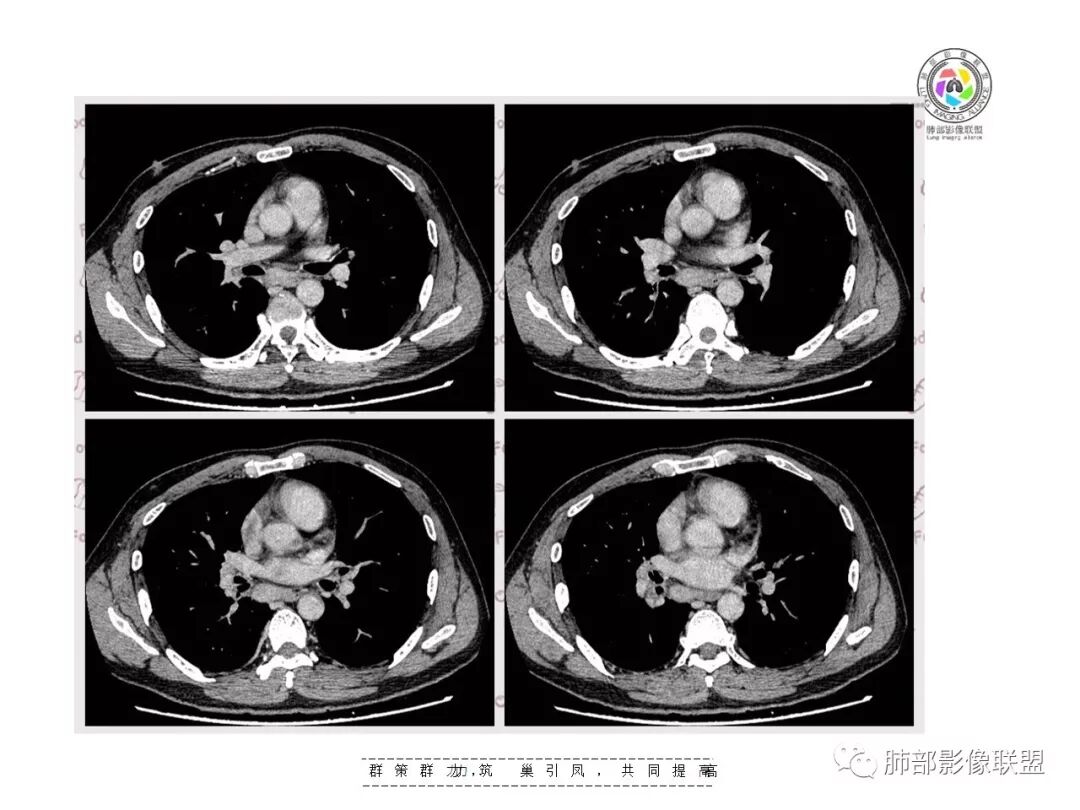

【影像资料】

王秀仙东宁市第二人民医院影像科:晨读:右肺下叶实变及磨玻璃影,边缘有收缩有膨隆,部分支气管进入扭曲扩张,磨玻璃影边缘清晰,实变影明显强化,内可见血管造影征,纵膈及肺门淋巴结肿大并强化,考虑粘液腺癌。

登封市三康医院(刘权威):右下肺肺不张,磨玻璃影,边缘清楚,空气支气管征,增强有强化,纵膈及右肺门淋巴结肿大并强化,考虑恶性肿瘤,粘液腺癌可能。

右肺门区淋巴结增大,融合,密度均匀,均匀强化